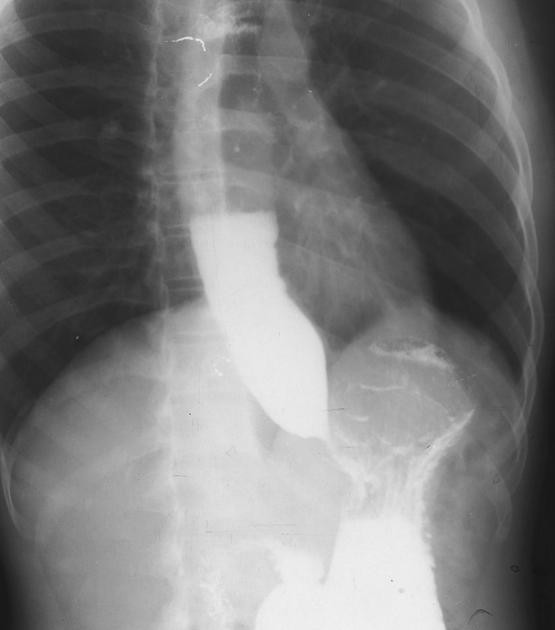

kalazya hastalığı, 3 yaşında da, 5 yaşında da, 90 yaşında da gözlenebiliyor.Akalazya hastalığı yemek borusundaki hareket bozukluğu olarak tanımlanmaktadır. Akalazyanın kelime anlamı gevşeme güçlüğüdür. Yutma ile meydana gelen kasılma dalgası lokmayı yemek borusundan mideye doğru iletir. Bu sırada yutmayla birlikte alt sfinkterde (büzgen kas) gevşeme meydana gelir ve lokmanın mideye geçişi sağlanır.

Alt sfinkter olarak adlandırılan bölge dinlenme halinde devamlı olarak kasılı durumdadır. Alt sfinkerın dinlenme halinde dahi devamlı olarak gevşemesi reflüye neden olurken; yutma sırasında gevşememesi ise akalazyaya neden olmaktadır. Hastalığın tedavi edilmemesi durumunda yemek borusu kanseri riskinde artış görülür.